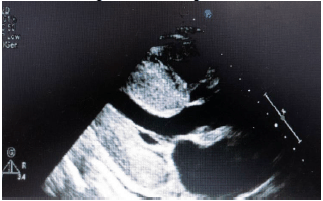

Paciente do sexo masculino de 75 anos, iniciou há cinco anos quadro de episódios recorrentes de dispneia aos esforços e edema de membros inferiores necessitando frequentemente buscar atendimento médico de urgência, não é portador de doença hipertensiva nem de outras comorbidades. Na última visita ao setor de urgência, apresentou-se com quadro clínico de insuficiência cardíaca biventricular e edema de extremidades. À investigação com exames complementares foi realizado ECG que evidenciou complexos QRS de baixa voltagem.

Assinale a alternativa correta que contém o provável diagnóstico, de acordo com os dados acima e a imagem ecocardiográfica abaixo.